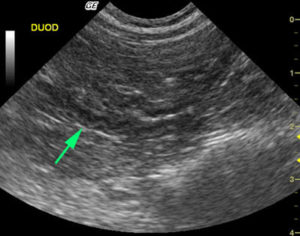

Но более информативным методом диагностики является ультразвуковое исследование. Одним из важных диагностических признаков в этом случае являются диффузные изменения железы. Контуры органа при этом могут быть неровными, а ее размеры, как правило, находятся в пределах нормы.

Фиброз поджелудочной железы не является самостоятельным заболеванием. Этим термином обозначают патологические изменения органа, которые обычно являются признаком хронического панкреатита. Фиброз определяется на УЗИ. Как правило, он не сопровождается симптомами, поэтому становится случайной находкой врачей при плановом обследовании пациента.

Клинических признаков фиброз не имеет. Его можно увидеть на УЗИ. Замещение паренхимы соединительной тканью видит патологоанатом при вскрытии больного. А вот определить фиброз по симптомам нельзя.

Важный метод диагностики фиброза поджелудочной железы – ультразвуковое исследование органов брюшной полости (УЗИ брюшной полости). Определяется диффузное повышение эхогенности органа, структура неоднородная, размеры уменьшены; возможно выявление расширения вирсунгова протока.

Более информативна эндоскопическая ультросонография, которая позволяет выявить линейные тяжистые включения разной протяженности и формы, бугристость контуров, гиперэхогенность паренхимы. При проведении ЭРХПГ выявляются изменения протокового аппарата, вызванные образованием рубцов.